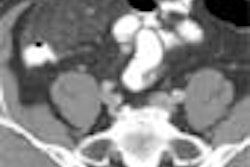

Now researchers from the Mayo Clinic in Rochester, MN, have produced intriguing results with the aid of dual-energy CT technology, distinguishing iron from calcium deposits in a plaque model, and potentially enabling the differentiation of hemorrhagic from calcific plaque.

Unstable plaque, the kind more likely to trigger a fatal clot, is characterized by intraplaque hemorrhage and subsequent iron deposits, which may be detectable with dual-energy CT. For more on the Mayo experiment, just click on our Insider Exclusive story, published for CT Digital Community subscribers before it is made available to our other members.